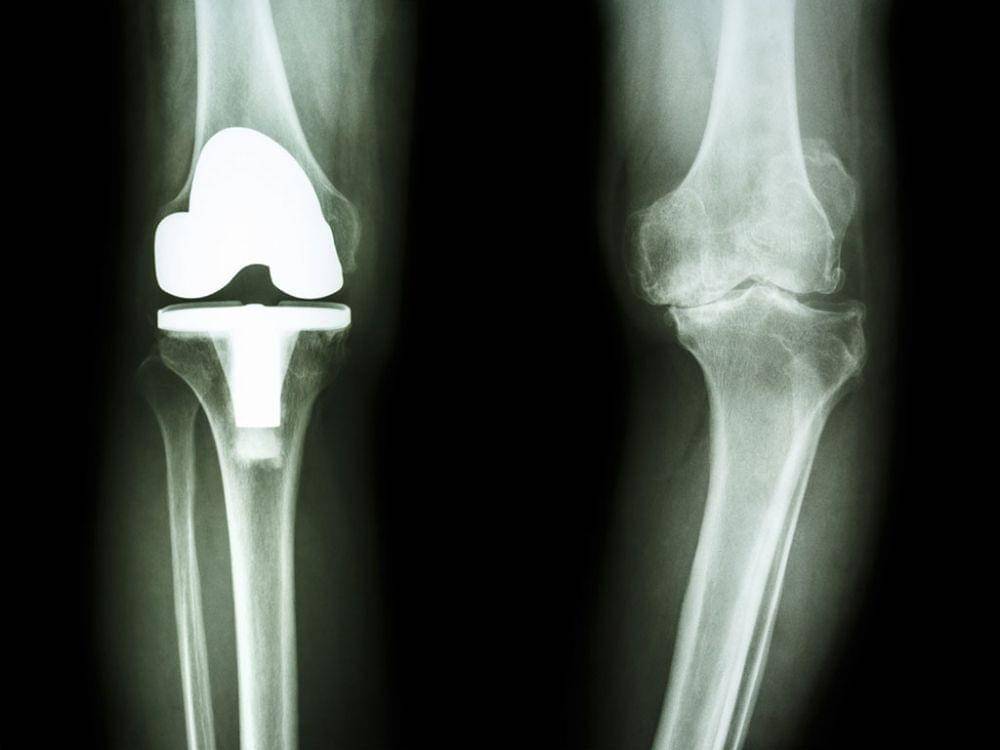

5. Penggantian lutut

Knee Replacement atau penggantian lutut dilakukan ketika sendi lutut telah aus, dan paling sering sebagai akibat dari arthritis. Kamu mulai bisa berhenti menggunakan alat bantu berjalan dan melanjutkan aktivitas normal sekitar enam minggu setelah operasi.

Namun, mungkin diperlukan hingga tiga bulan sampai rasa sakit dan bengkak untuk berkurang. Diperlukan waktu hingga satu tahun agar pembengkakan di kaki benar-benar hilang.